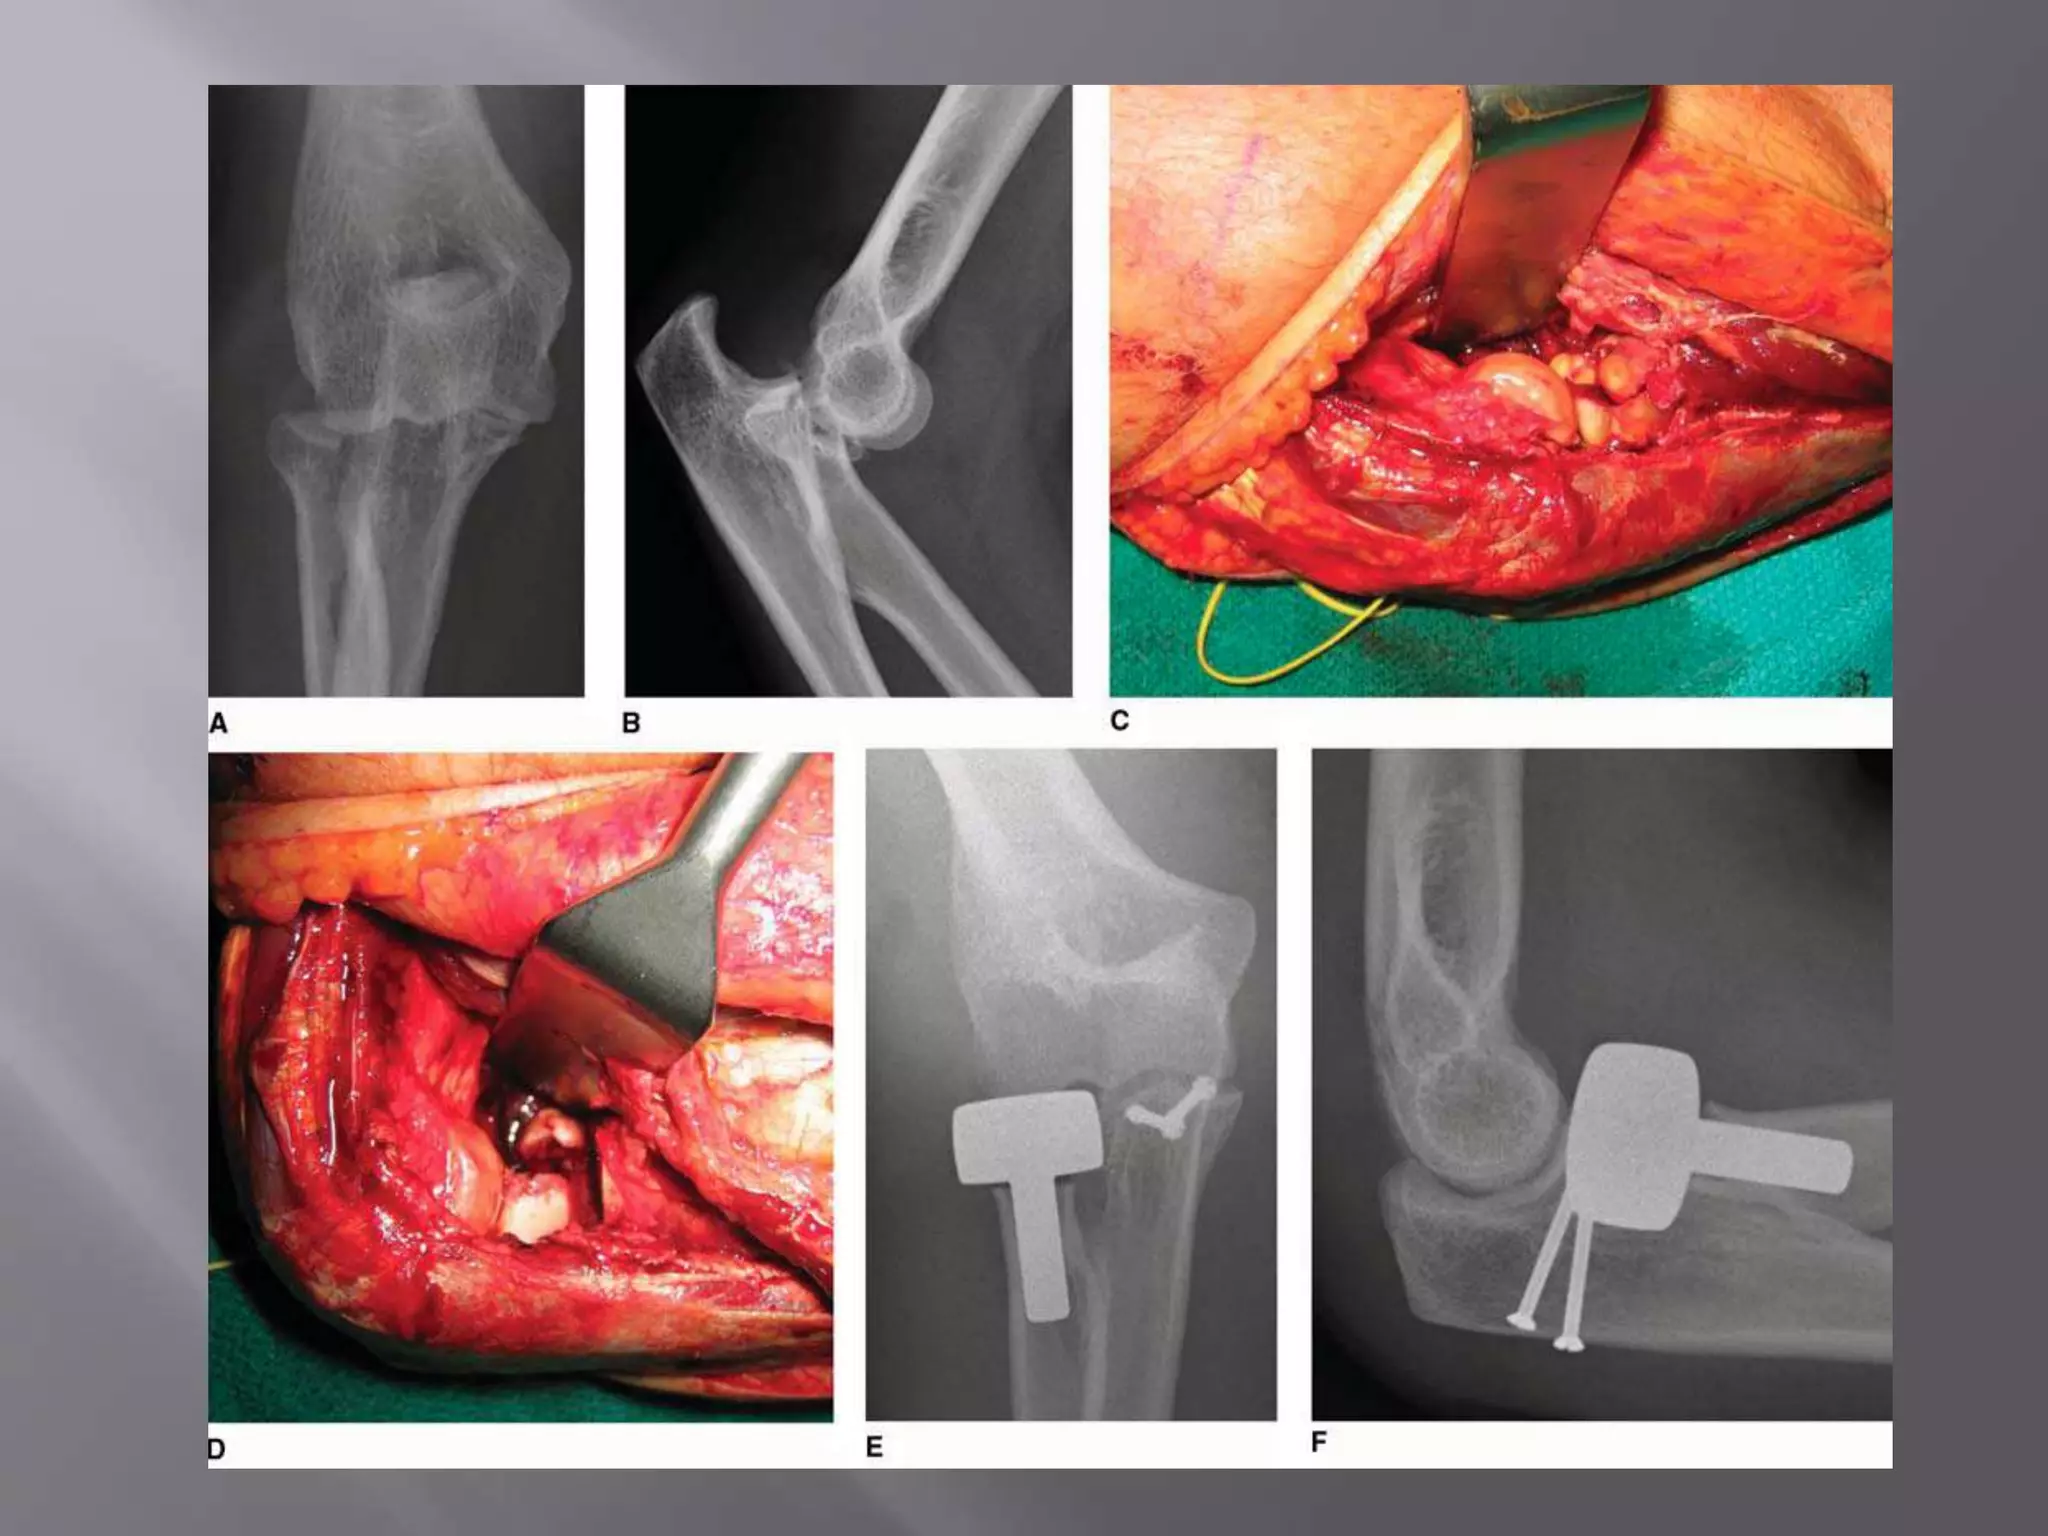

This document discusses the terrible triad injury of the elbow, which involves fractures of the radial head, coronoid process, and posterolateral dislocation. It notes the poor outcomes associated with this injury like stiffness, instability, and hardware failure. The document outlines the relevant anatomy of the medial collateral ligament and lateral uncular collateral ligament. It describes the mechanism of injury, known as the fall on an outstretched hand, and how the ligaments and capsule fail in this injury. Diagnostic imaging and classification of radial head and coronoid fractures are covered. Treatment options including observation, resection, open reduction internal fixation, and replacement are presented. Surgical approaches and techniques are also outlined.